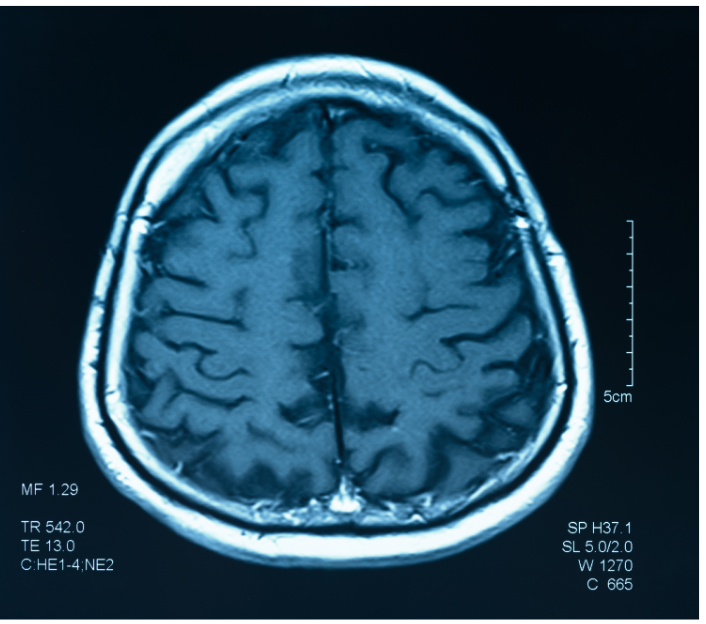

โรคมะเร็งสมอง เกิดจากอะไร?

คือโรคที่เกิดจากเนื้องอกที่เป็นเนื้อร้ายบริเวณสมอง และเติบโตขึ้นอย่างรวดเร็ว อาจเกิดขึ้นเองที่เนื้อเยื่อสมอง หรือจากการลุกลามของมะเร็งจากอวัยวะอื่น โดยมีปัจจัยเสี่ยงต่าง ๆ ที่อาจทำให้เกิดโรคมะเร็ง เช่น การสัมผัสสารเคมี การสูบบุหรี่ หรือประวัติการเกิดโรคมะเร็งของสมาชิกในครอบครัว ส่งผลต่อร่างกายและการใช้ชีวิตประจำวัน เช่น ปวดศีรษะ เป็นลม คลื่นไส้อาเจียน ปัญหาด้านการทรงตัว ความคิด สติปัญญา ความทรงจำ การพูด การมองเห็น บุคลิกภาพ และอาจเป็นอันตรายต่อชีวิต